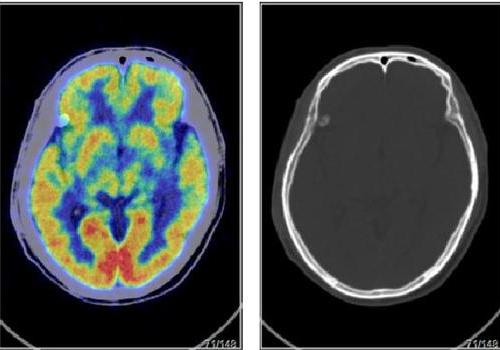

年 龄:52岁检查项目:全身临床诊断:肿瘤标志物升高待查显像剂(种类/剂量):18F-FDG/9. 4mCi筒要病史:咳嗽2月,为干咳,不伴胸闷、胸痛等症状。就诊于当地医院,行胸部CT 示两肺多发小结节灶(3mn)。查肿瘤标志物示CEA 4.62ng/ml (<4. 5),余 肿瘤标志物未见增高。查胃镜示浅表性胃炎。现患者纳差,偶有咳嗽。无进食;有手术史,阑尾炎术后;无结核史;无外伤史;无糖尿病史;有 肝炎史,黄疸性肝炎病史;无传染病史;无其他疾病史;无吸烟史;无饮酒 史;有家族史,母亲肺癌;月经史:LMP: 2020-7-10;意识:清楚;空腹血糖:5.5 mmol/L;检查结果:禁食状态下,静脉注射18F-FDG约1.5小时后行PET/CT全身显像(3IHT0F采 集,TrueX重建),图像显示清晰。大脑各部显像清晰。大脑皮质内放射性分布均匀,双侧額叶、顶叶、顺叶、枕叶放射性分布对称,双側基底节、丘脑、双側小脑放射性分布对称,未 见明显放射性摄